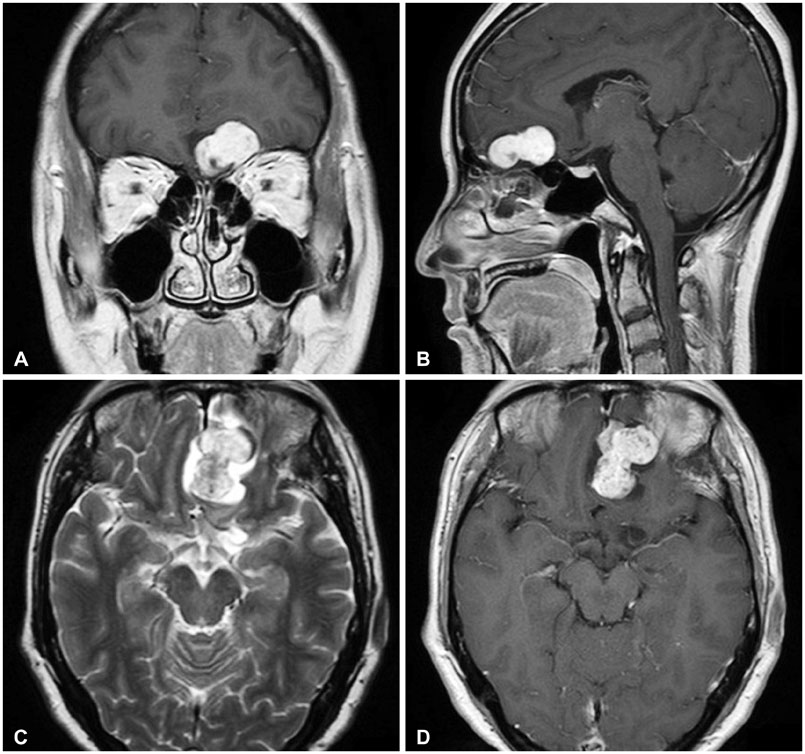

- The olfactory groove schwannoma is a quite rare tumor. We report a case of a 49-year-old woman with an olfactory groove schwannoma attached to the cribriform plate without olfactory dysfunction. She had no specific neurological symptoms other than a headache, and resection of the tumor showed it to be a schwannoma. About 19 months after the operation, a follow-up MRI showed no evidence of tumor recurrence. Surgical resection through subfrontal approach could be one of the curative modality in managing an olfactory groove schwannoma. An olfactory groove schwannoma should be considered in the differential diagnosis of anterior skull base tumors.